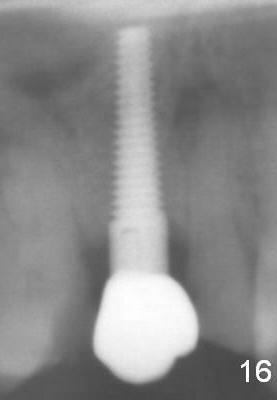

A 72-year-old man is a bruxer with #3 cusp fracture with chronic periapical radiolucency (Fig.1 *) and #4 acute crack. It appears reasonable to take care of emergency (#4 extraction and immediate implant (Fig.3-7: 4.5x20 mm, 45 Ncm)) followed by root canal therapy or extraction for #3. Eight (Fig.8) and 14 (Fig.9-11) days postop, the patient is doing fine and the wound heals normally. But he does not agree any treatment for #3, since it is asymptomatic in spite of a fistula associated with the tooth (Fig.8,9 >). Three months postop, the patient is still asymptomatic and is ready for #4 restoration since the tooth #28 cracks. Follow-up PA shows the persistent distal gap (Fig.12 >, as compared to Fig.4), accompanied with crestal bone resorption (*). Clinically the implant has mild mobility and light tenderness. The patient still refuses #3 treatment. It appears that the implant has failed to osteointegrate. In brief, do not place an immediate implant next to active infection.

Five and a half months postop, the distal gap appears to have reduced (Fig.13 >). Clinically the implant is stable and is ready for restoration. It is advisor able to watch those asymptomatic immediate implants with minimal mobility. It takes time to osteointegrate the immediate implant considering the peri-implant space.

Eight months post cementation, CBCT shows periapical infection of the neighboring teeth (Fig.14 *). There is still apical bone for a longer implant (Fig.14 green line, Fig.15 *). The implant functions 1.5 years post cementation. When the implant at the lower bicuspid fails, the patient reveals that he is a diabetic. The latter is the main reason of delayed healing.